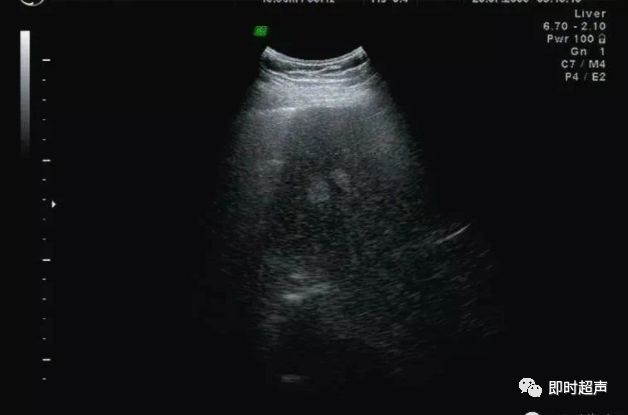

非均匀性脂肪肝:脂肪肝形成和发展过程中,受到门静脉血流中胰岛素和胰高血糖素含量以及肝内门静脉-体腔静脉交通支等因素的影响,脂肪浸润可表现为非均匀性。

依据超声表现可分为四型:

1、局灶浸润型:呈局灶性强回声,无包膜,边界不清,后方可伴衰减。

此型需与肝转移癌及肝血管瘤鉴别。

2、多灶浸润型:在回声相对正常的肝内,可见多发强回声。

3、叶段浸润型:一部分区域为低回声,其它区域为强回声。

此型需与肝转移癌鉴别,此型肝内血管走行正常,无靶环征及牛眼征。

4、正常肝残留型:肝脏弥漫性回声增强,其内可见低回声区,为轻度脂肪浸润或性对正常肝残留区,好发于胆囊床、门静脉主干周围。